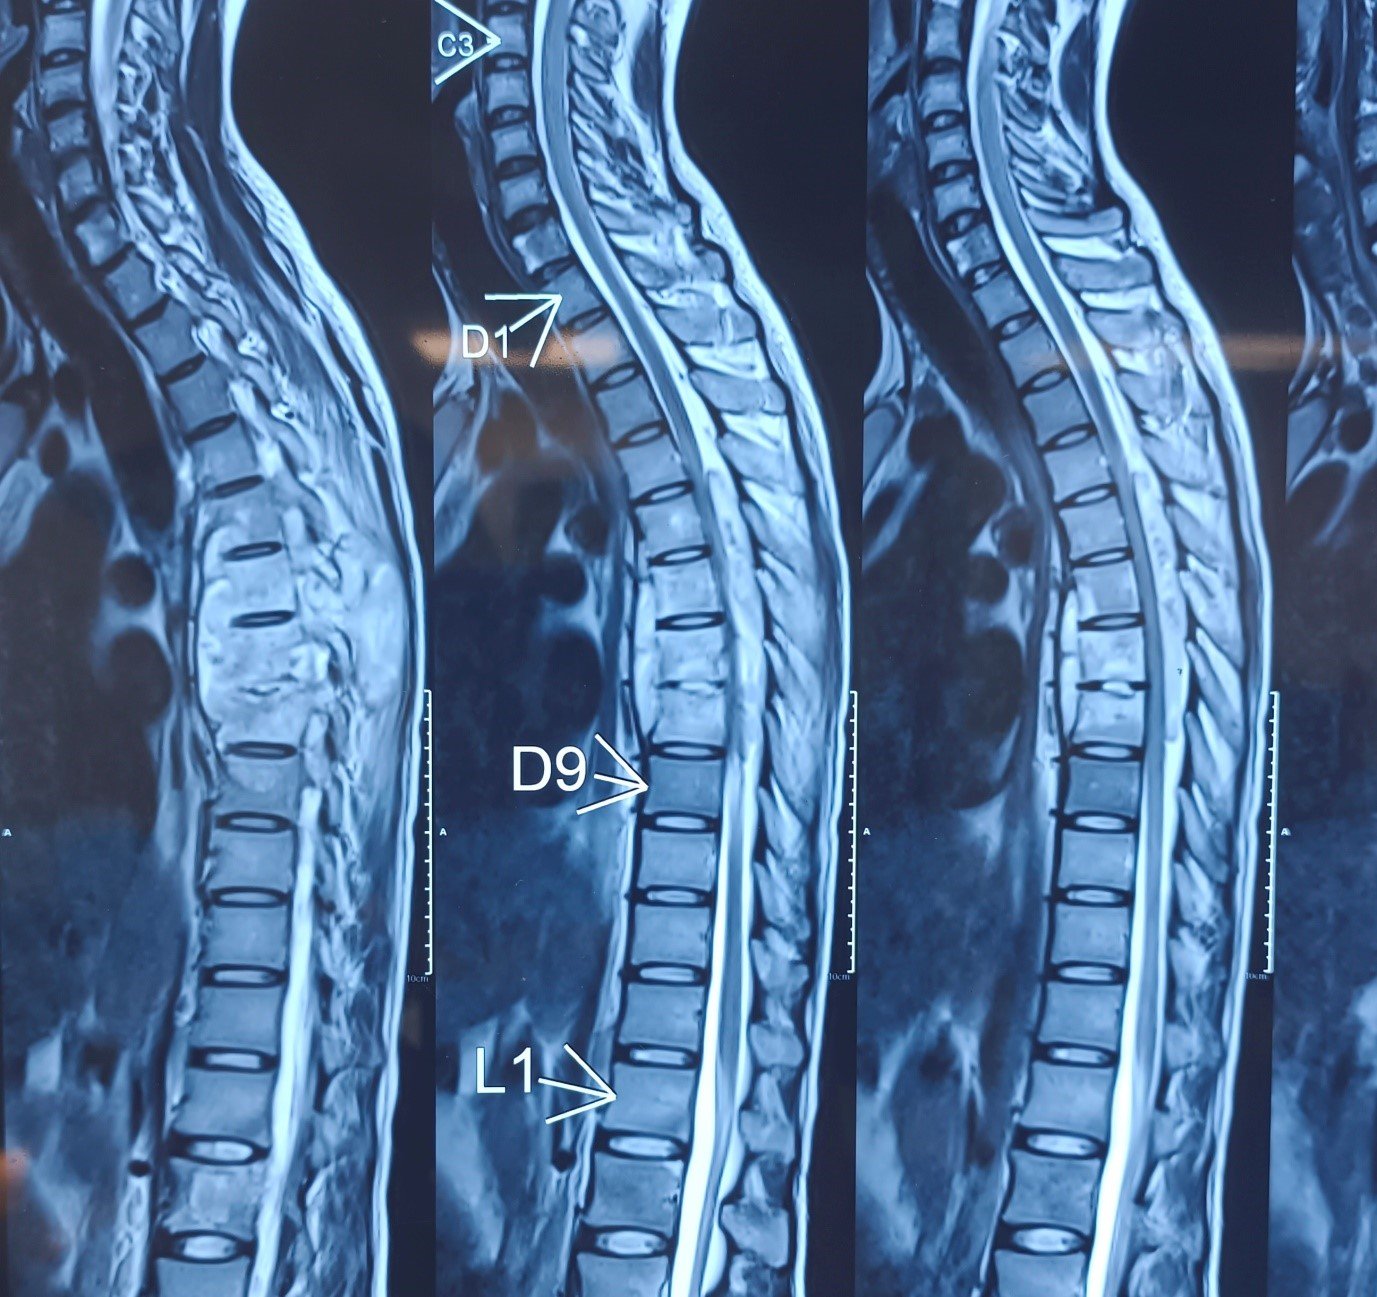

Cervical Disc Prolapse with Spinal Cord Compression

Special Cases Cervical Disc Prolapse with Spinal Cord Compression Condition:Cervical disc prolapse in which the herniated disc compresses the nerve roots and spinal cord, often associated with spinal cord edema. Symptoms:Neck pain, numbness in hands, weakness, difficulty in walking, and coordination problems. Treatment:Anterior Cervical Discectomy and Fusion (ACDF) – The…